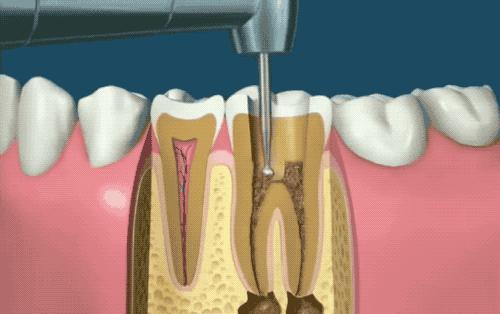

先用牙钻在牙齿上钻一个洞,进入牙髓腔。接着牙医根据实际情况选择不同尺寸的钻头将感染的牙本质去除,露出来牙根管(牙医的小钻伴随着呲呲喷溅的凉水,算是我童年最大的噩梦...)

根管预备

使用细细的根管锉,除去根管内的残留物,并且反复冲洗管道。在手工操作时,会使用型号逐渐递增的根管锉...小心地清理和修正根管。一颗牙会有一个或多个根管。这是最痛的一步,好男儿也会流泪。

一边进行根管预备,同时还要不停对根管进行冲洗,使得根管内达到无菌的状态,真是想起那个场景就要抹一把辛酸泪...